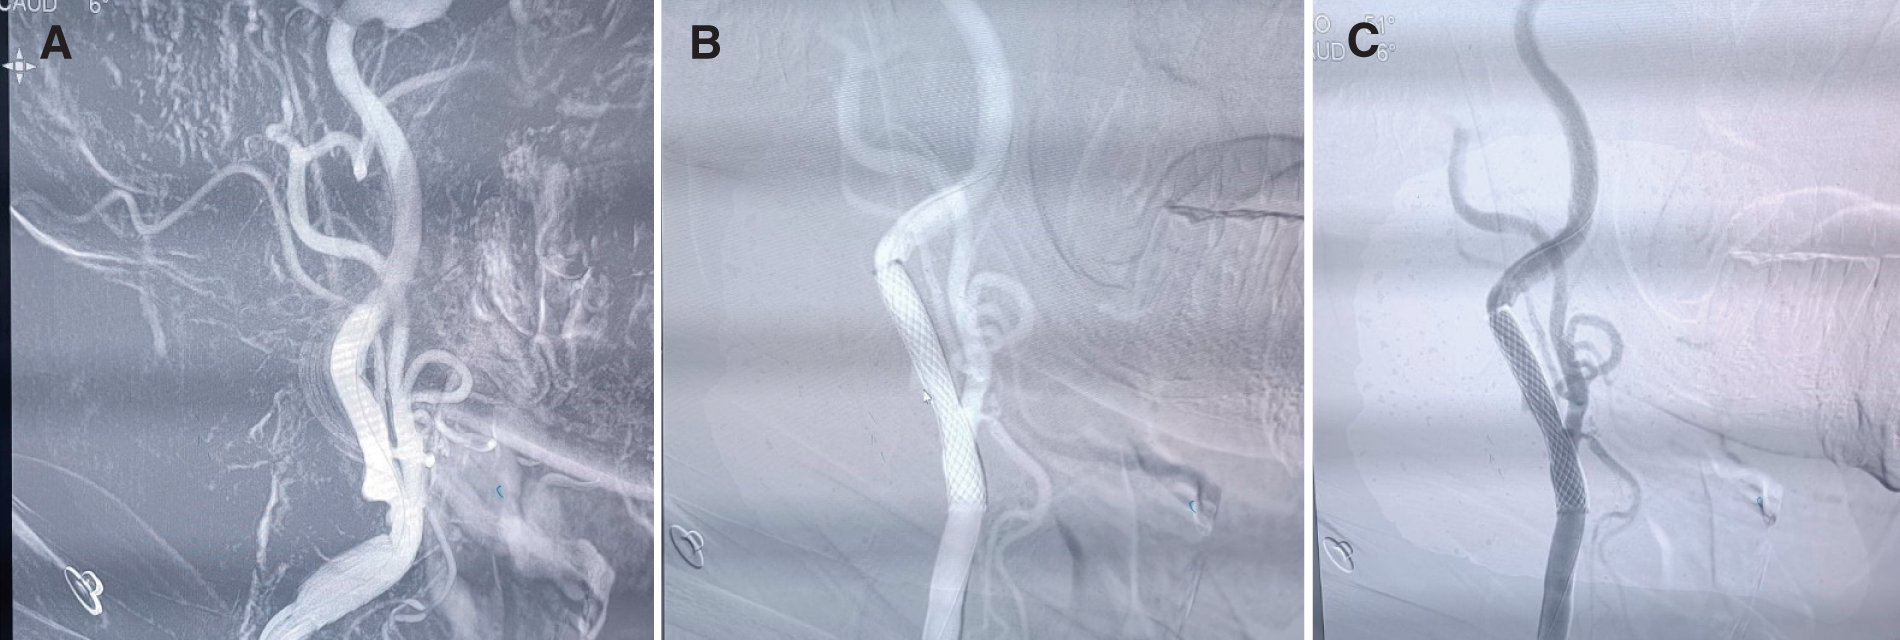

A total of 62 patients were included in this retrospective study. Fifty-three patients were male (85.5%), while 9 were female (14.5%). The mean age of patients was 60.2 ± 9.6 years. All patients were treated successfully with deployment of a single closed-cell stent (Carotid WALLSTENT; Boston Scientific). The site of stent deployment was the left internal carotid artery (ICA) in 43 patients (69.4%) and the right ICA in 19 patients (30.7%). NIHSS before the procedure was 0 in 47%, 3–5 in 34% and 6–9 in 19% of patients. The mean NASCET was 76% ± 10%. Predilation angioplasty was needed in 16 (25.8%) patients and postdilation angioplasty in 58 (93.6%) patients. There were no major complications, including cerebral infarctions. Significant bradycardia occurred in 2 patients and responded immediately to atropine, but no profound hypotension developed in any patient. One patient had transient dysarthria, but diffusion-weighted (DW)-MRI was negative. Three patients developed mild local hematoma, and 1 patient had a pseudoaneurysm. No stroke, myocardial infarction, or in-stent thrombosis was documented during the 30-day follow-up. A summary of the baseline characteristics and risk factors is presented in Table 1, and a case example illustrating a patient with significant right ICA stenosis before and after the procedure is shown in Fig. 1.

CAS procedureAll CAS procedures were performed by a single interventional neurologist (2 years of training as a subspecialty in Egypt), and the stents used were all Carotid WALLSTENT (Boston Scientific, Marlborough, MA, USA). The patients should be on dual antiplatelets (aspirin 75 mg and clopidogrel 75 mg for at least 5 days before the procedure, or aspirin 75 mg and ticagrelor 90 mg twice daily). In patients who were on aspirin only, they received a ticagrelor loading dose of 190 mg at least 2 hours before the procedure. Dual antiplatelets were continued for 6 months after the procedure, then switched to a single antiplatelet, usually aspirin 100 mg once daily. If financially feasible and the plaque was stable, the CAS procedure was performed early (within 2 weeks of symptom onset). In 14 patients with unstable hypoechoic plaque or mobile thrombus, the procedure was delayed, and duplex ultrasonography was repeated after 2 weeks and again after 1 month before proceeding with CAS.

The common femoral artery was used in all patients. Under local anesthesia, a short 10-cm Terumo (Terumo Medical, Tokyo, Japan) 8-Fr sheath was inserted into the common femoral artery, followed immediately by the administration of 5000 international units of heparin. First, a 5-Fr diagnostic catheter Bern (Cordis, Miami Lakes, FL, USA) was used to perform imaging of all arteries, and then an 8-Fr guiding catheter (Mach1 SoftTip; Boston Scientific) was placed in the common carotid artery under continuous heparin infusion. If angioplasty was needed before stenting, then a 2.5 × 20-mm balloon was used, and a 5 × 20-mm balloon was used for post-dilatation angioplasty, with a goal of covering the lesion and achieving residual stenosis of less than 30%. Atropine was kept ready in a syringe for any bradycardia. After the stent was deployed, final imaging of the vessels was performed to exclude distal embolism, and the catheter was removed. Finally, manual compression was applied to the access site for 20–30 minutes to prevent bleeding, and the patient was monitored in the intensive care unit (ICU) overnight for any complications such as bleeding or stroke.